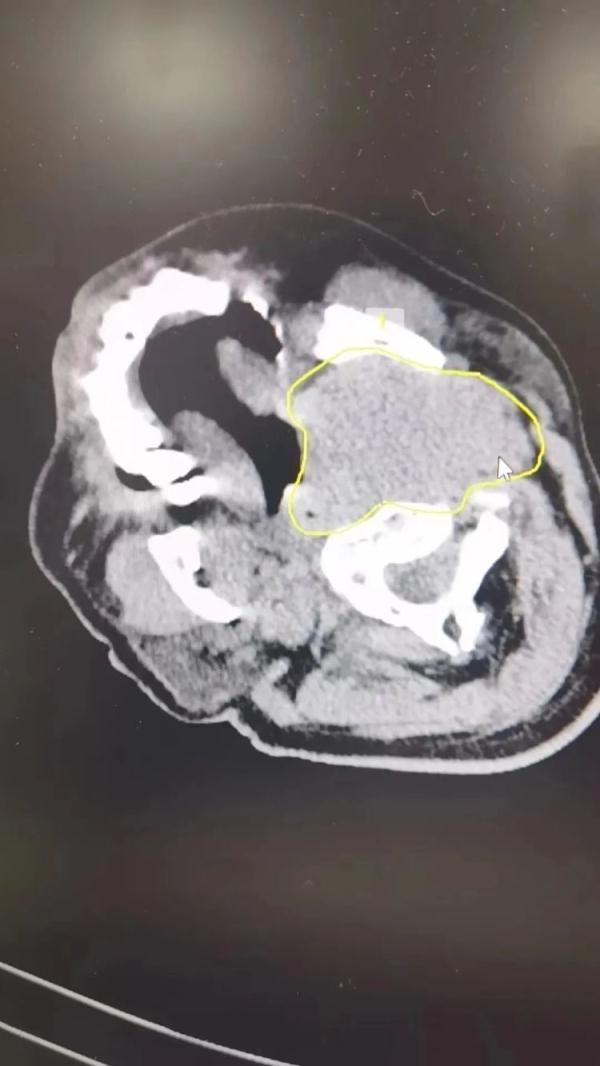

很快,雷先生在医院接受了头颅CT、MRI等一系列检查,医生发现其有脑积水,此外左侧颈静脉窦处有一个4x6cm的病灶。

(下图黄圈处)

接诊的福州市第一总医院肿瘤整合科骆华春医生初步诊断,雷先生反复晕厥休克,就是这个鸡蛋大的病灶,压迫颈静脉窦引起的,查到了病灶,明确诊断还没结束。这个病灶是好是坏还不清楚,骆华春马上为雷先生进行病理穿刺,并联系医院病理科黄玉钿主任,最终通过24小时快速病理诊断,明确病理结果为“恶性弥漫大B淋巴瘤”。